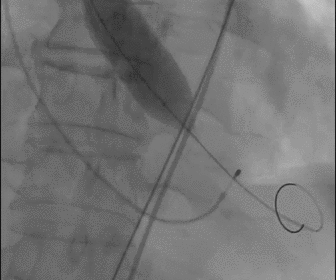

瓣膜释放完毕